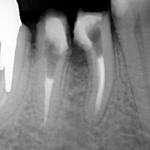

Na czym polega premolaryzacja?  Jest to przecięcie wzdłuż zęba trzonowego, z reguły dolnego, na dwie części tak aby powstały dwa przedtrzonowce (zdjecie poniżej)

Jeśli przeleczony kanałowo ząb jest wrażliwy a zdjęcie rentgenowskie wykazuje defekt kostny w obrębie bifurkacji  czyli w miejscu rozdzielenia korzeni, wszystko wskazuje na to, że dno komory zęba jest zniszczone, a nieszczelnośc ta spowodowała zniszczenie kości w tym miejscu. Zachowawcze leczenie jest niemożliwe.

Jeśli chce się uratowć taki ząb, jedynym rozwiązaniem jest separacja czyli premolaryzacja. Zabieg ten wykonuje się w znieczuleniu miejscowym. Wiertłem przecina się ząb, tak by odsłonić całą perforację dna komory. Stwarza się w ten sposób dwa oddzielne zęby. Miejsce przecięcia należy bardzo dokładnie i szczelnie zabezpieczyć kompozytem. Jest to dość trudne w wilgotnym, podziąsłowym miejscu. Jeśli leczenie kanałowe jest nieszczelne należy je wykonać ponownie.